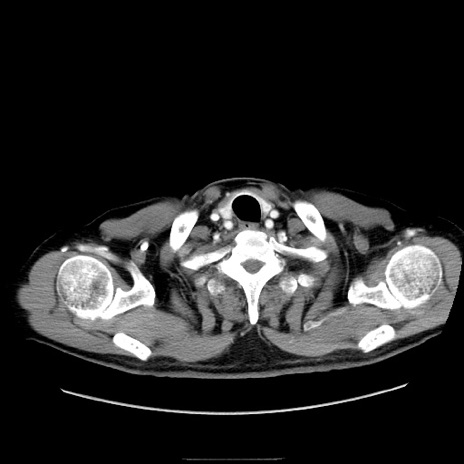

症例30(横断像)

【症例】80歳代男性

【主訴】臍周囲痛

【現病歴】約6時間前から臍下部痛が出現。次第に腹部膨隆・背部痛も生じてきたため来院。背部痛の場所は変化しない。

【身体所見】意識清明、BT 36.3℃、BP  131/87mmHg、P 87bpm、SpO2 100%(RA)、臍周囲自発痛・圧痛あり、反跳痛なし、自発痛部位に一致して板状硬あり、腹部膨隆、腸雑音減弱、CVA tenderness両側陰性。

【データ】WBC 19600、CRP 0.33